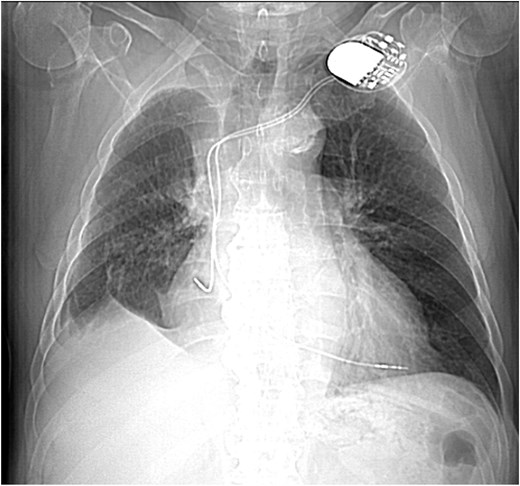

His post-operative clinic follow-up was satisfactory, with well-healed wounds and imaging showing volume loss but no sign of recurrence (Fig. 5).

Scout CT scan showing postoperative volume loss in right hemithorax.